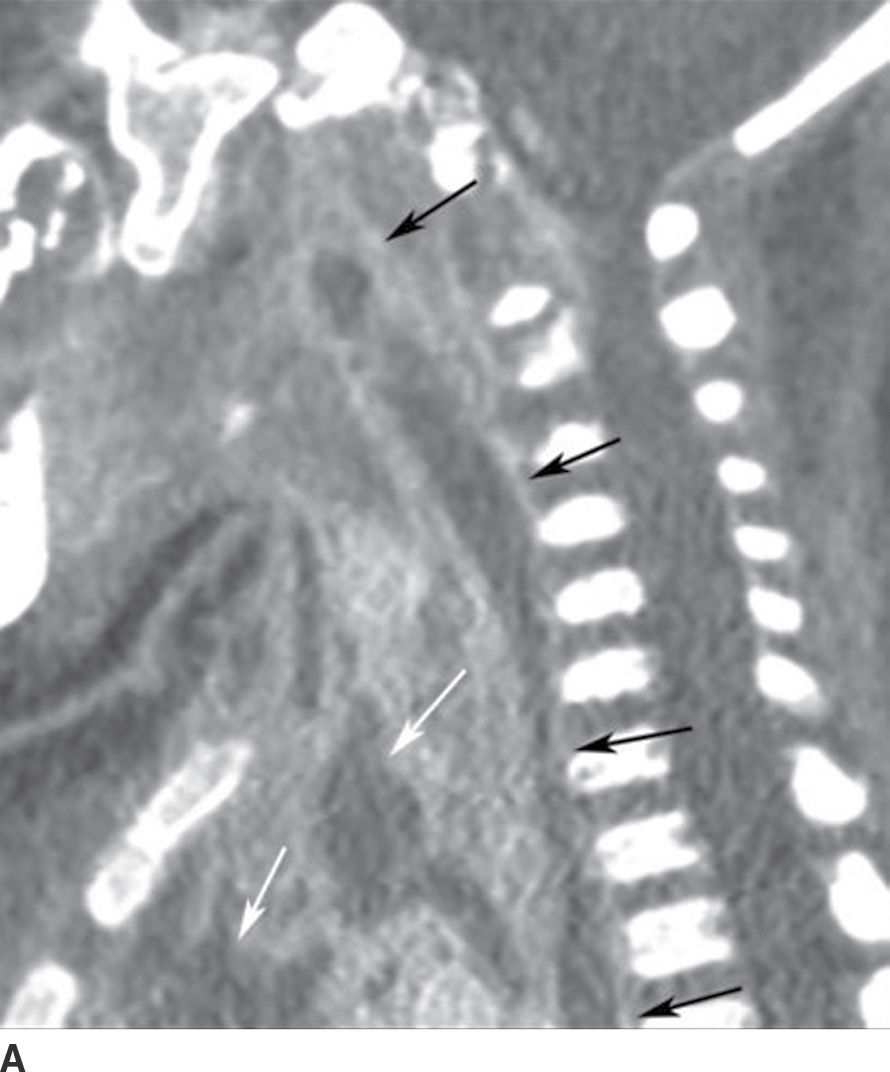

From www.researchgate.net

A & B Axial cuts of suprahyoid and infrahyoid region showing Danger Space Mediastinum The danger space (alar space) is a deep compartment of the head and neck located posterior to the retropharyngeal space and. The danger space lies behind the true retropharyngeal space, and courses more inferiorly than the true retropharyngeal space, running into the posterior mediastinum until the level of. An infection of this space can thus spread to. Inferiorly, the danger. Danger Space Mediastinum.